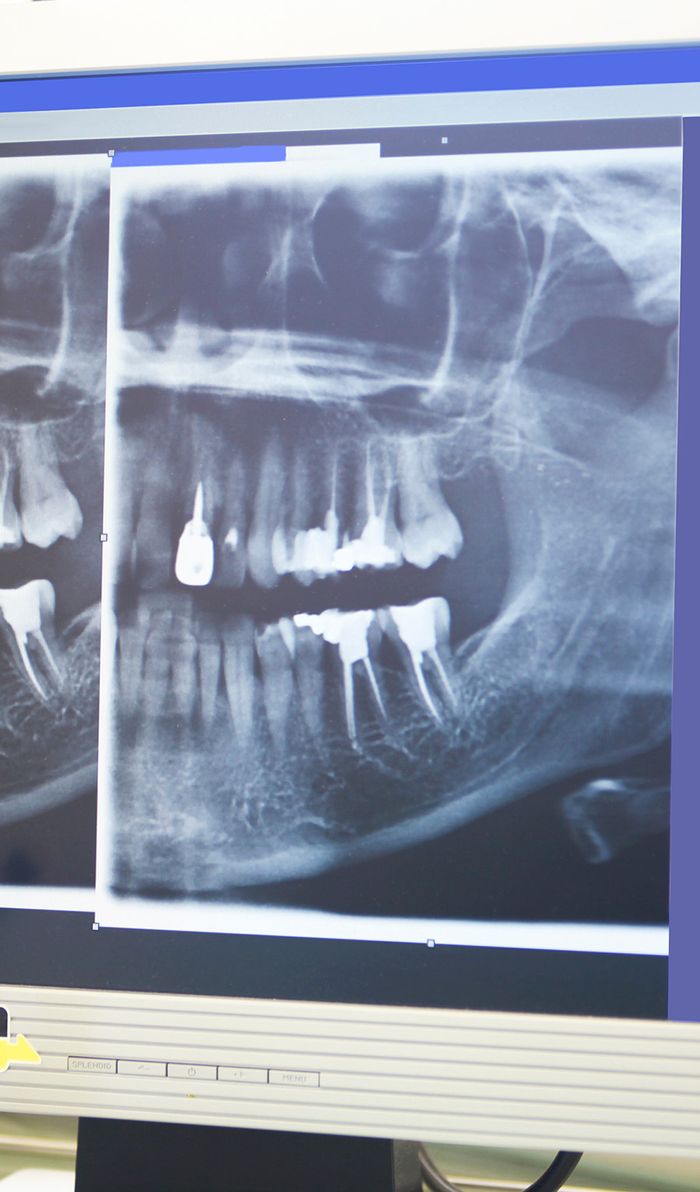

To find the source of your dental pain, your dentist will begin by performing a comprehensive exam and review of your x-rays to get a complete picture of your oral health. If your tooth is infected, they will determine the extent of the infection to decide if root canal therapy will be an effective treatment. If you end up needing a root canal, your dentist will begin the therapy by numbing the treatment site, all the way down to the nerves. Your dentist will discuss sedation options with you before starting the procedure.